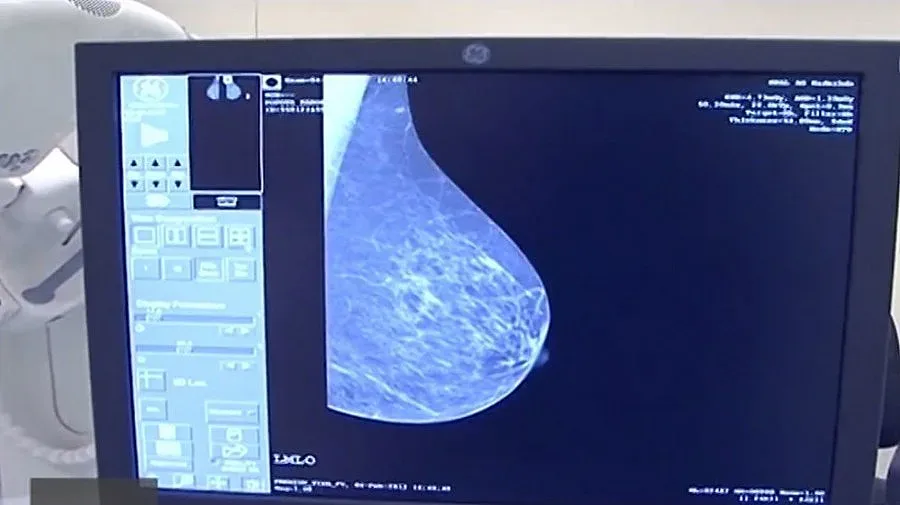

Почти всяка минута една жена в света умира от рак на гърдата. Заради тази статистика преди 7 години инженерът по биомедицинскатехника Кристина Близнакова започва да търси начини за по-прецизна и безопасна диагностика.

За разлика от досегашните двуизмерни технологии, българският проект е лесно приложим в практиката, защото е базиран на 3D модели на злокачествени тумори.

„Малки лезии, които не могат да бъдат открити в мамограма на гърда, могат да бъдат ясно открити с тази техника и не само да бъдат открити, но и да бъдат разграничени границите", обяснява доц. Близнакова. Засега учените се опитват да намалят облъчването, което според екипа е постижимо в близко бъдеще. А след като влезе в практиката, технологията може да бъде прилагана при рак на белия и на черния дроб.